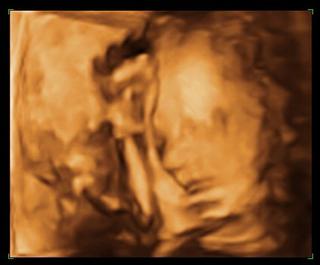

Po dlhej a úmornej očiste z nebies, som pri prvých náznakoch slniečka okamžite utekala navštíviť neďaleký park. Sediac na lavičke, dívajúc sa na nežné okvetné lístky sedmokrások. Po chvíli som otrhla zrak od strieborných okvetných lístkov lemujúcich malé žlté slniečka. 🙂 Zrak mi padol na párik, ktorý sa zničoho nič objavil predo mnou. On niesol v rukách plné nákupné tašky, ona sa knísavo, no predsa len rezko snažila držať s ním krok. Udivene som sa pozerala na tú chôdzu, no po chvíľke som zbadala jej zaguľatené bruško. Jej túžobný pohľad, ktorý hodila na lavičku vedľa tej mojej mi bol dôverne známy. 🙂 Zrejme sa malý nezbedník v brušku zobudil a potreboval sa len dobre ponaťahovať. Žene sa tvárou mihol ľahký kŕč. Potešene som sledovala, s akou Láskou prikladá On ruku na tú malú „výduť“. 🙂 S úžasom som sledovala, ako Láska naozaj dokáže robiť zázraky! 🙂

Aké? Predsa každý bezzubý školáčik už vie, že 1+1 = 2. No ja som pred sebou videla iný výsledok. Evidente má Láska na matematiku iný názor. 🙂 Ja som predsa jasne videla tento jednoduchý príklad s iným výsledkom… 1+1=3 🙂

Nádhera Lásky a zrodenia otriasla základmi aj kráľovnej vied. Viem, že neexistujú žiadne pravidlá, žiadne obmedzenia, žiadne prekážky, žiadne nemožné situácie či okolnosti. Stačí len čistá Láska v spojení so slovom CHCEM. Stačí ju prijať naplno do srdca a všetko ostatné prestáva fungovať. 🙂

Preto nezabudnime všetci! Na to aby mohol výjsť výsledok 1+1=3 stačia dvaja, ale ten tretí si zaslúži našu plnú pozornosť a úctu a to už odvtedy, odkedy sa nadšení rodičia dívajú v pôrodnici do perinky a unesene sa predbiehajú v chválospevoch na fyzickú podobu dieťaťa. Vyjadrenia typu „ chcela som, aby malo presne Tvoje oči“ sú totižto z tohto pohľadu úplne smiešne, pretože aj tak sa nevyhne neskoršiemu, pre mňa veľmi zábavnému faktu, že záporné vlastnosti sme podedili výlučne po „odporných svokrách, ujoch, či dokonca po dedkovom-pradedovi“ a aj to vždy výlučne zo strany partnera, pretože v našej rodine sa takýto bordel nenachádza. :lol: Majme preto na pamäti, že každý z nás je úplne a maximálne jedinečný.